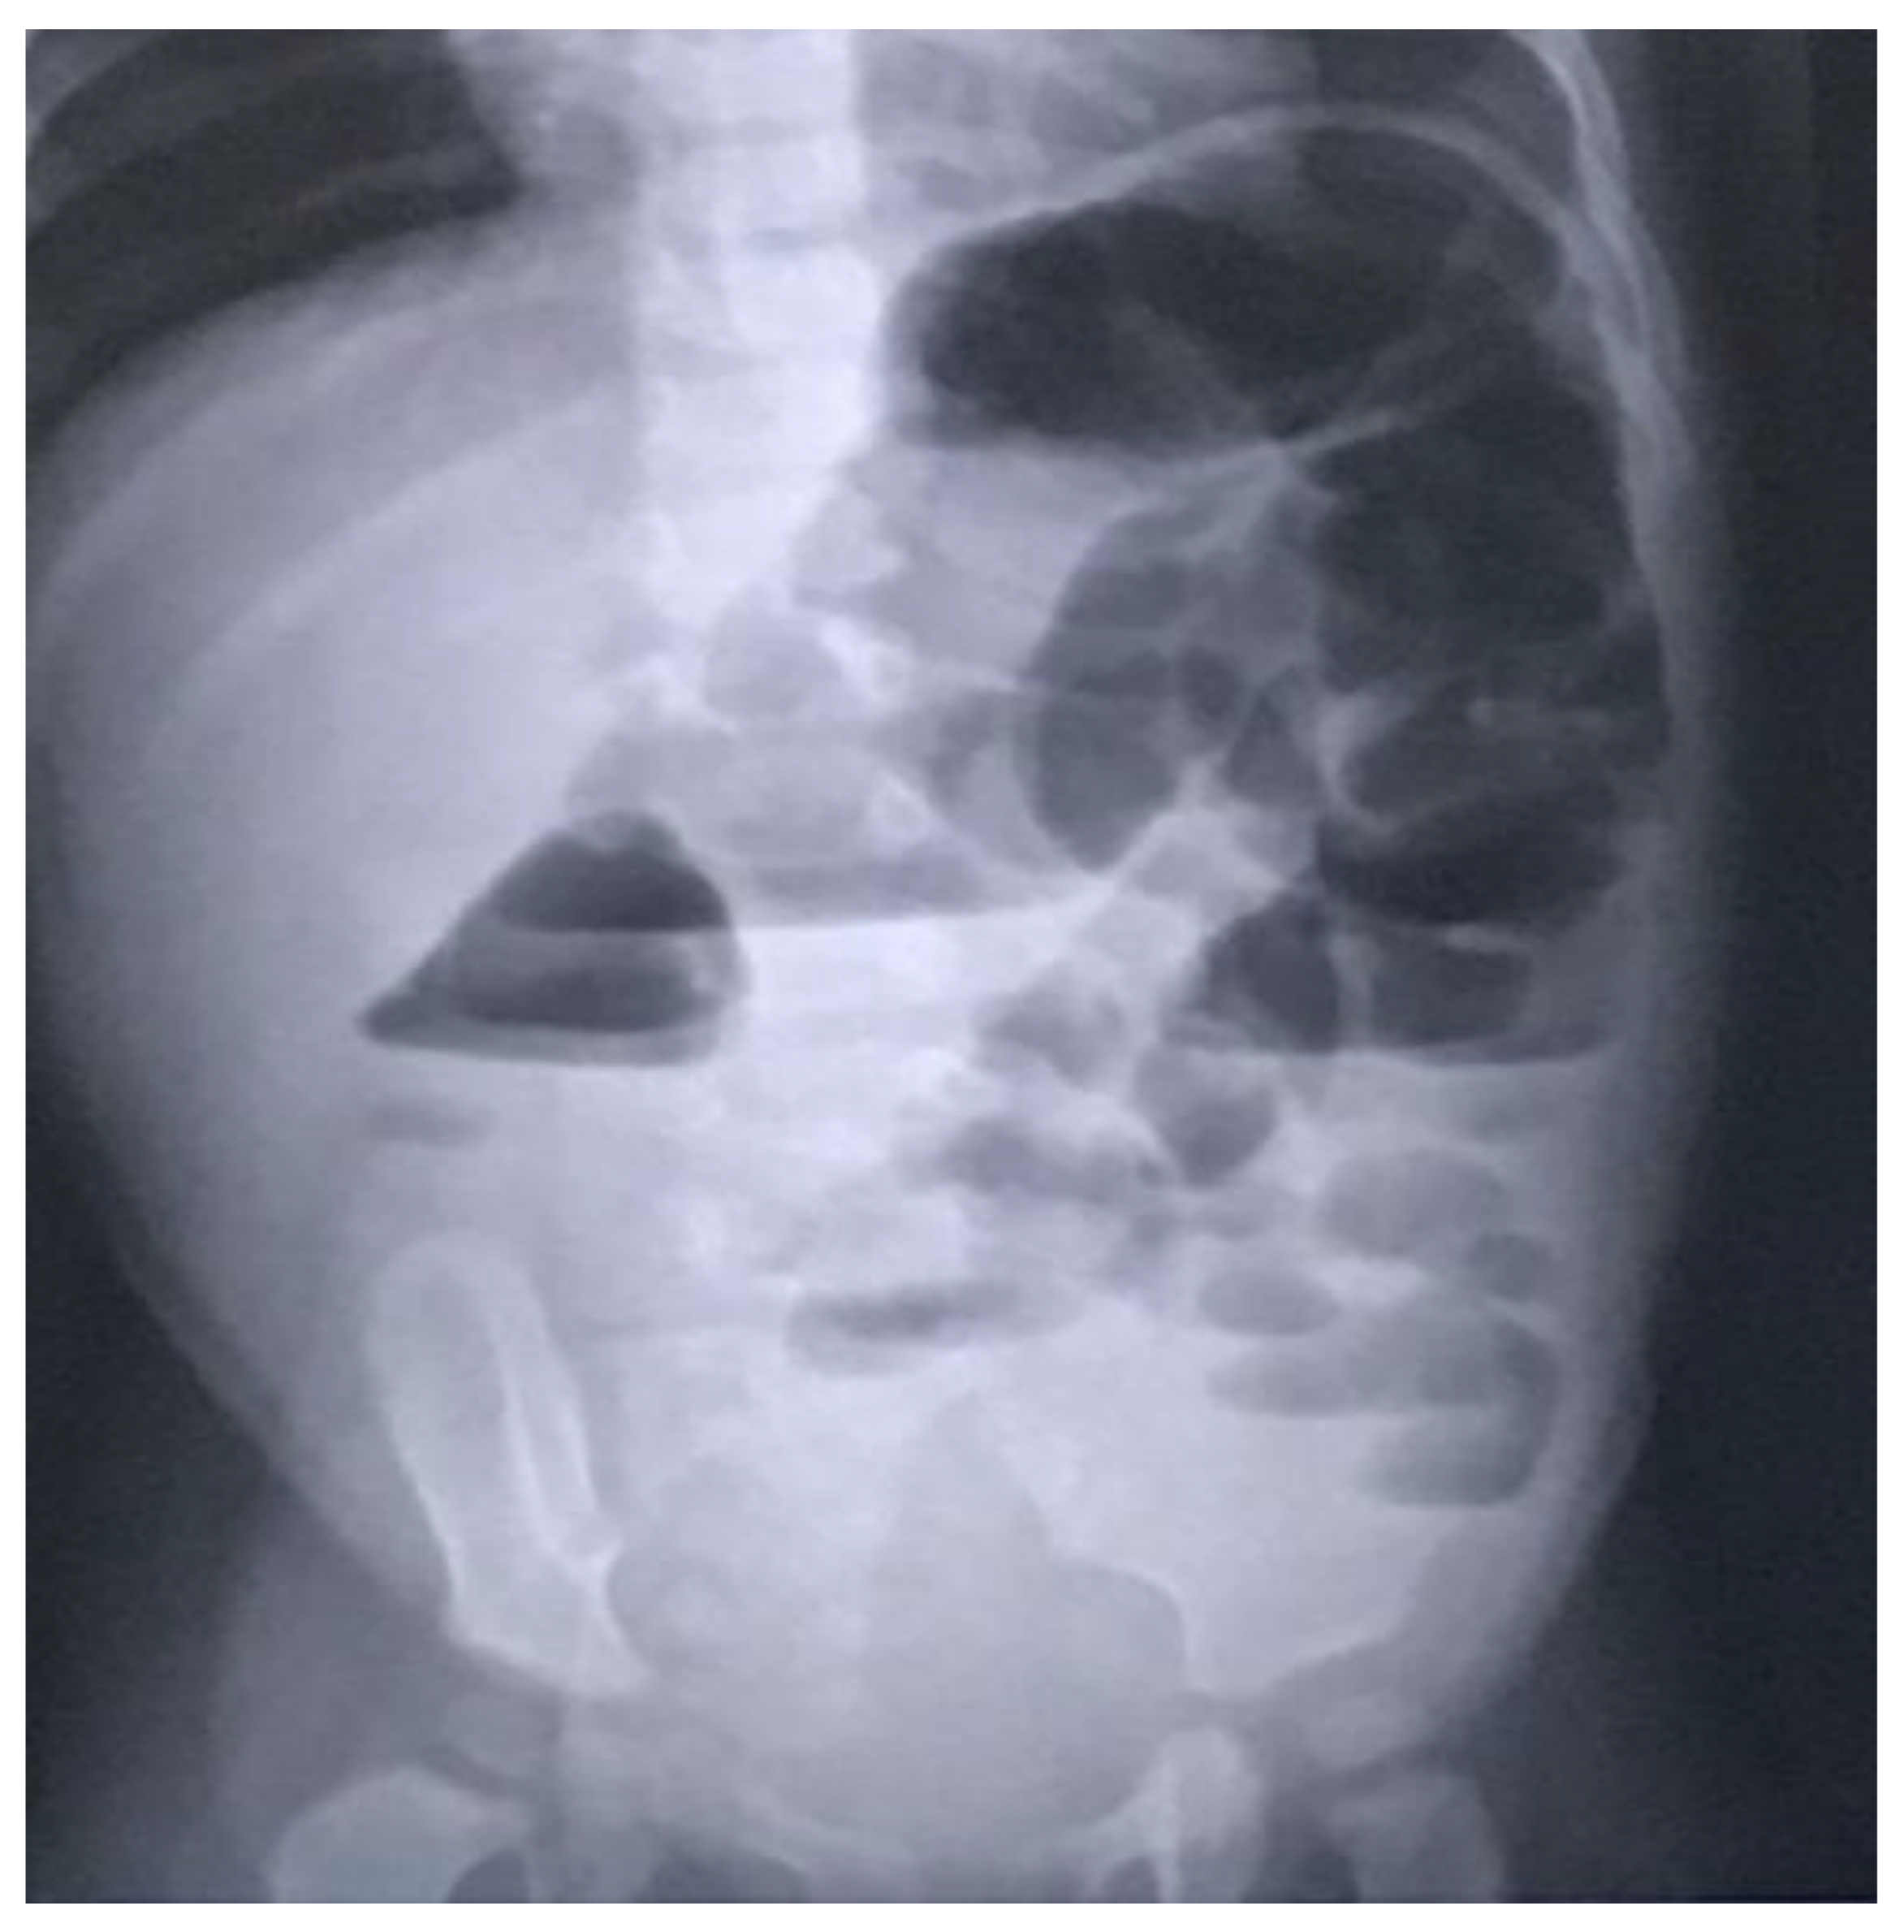

In light of the ongoing significant abdominal distension, an abdominal X-ray was conducted, revealing bowel dilation characterized by air-fluid levels and the absence of any luminal obstructive lesion (Figure 1).

Figure 1. Radiographic indications of bowel distension with discernible air-fluid levels and the nonexistence of any lesion causing luminal occlusion.